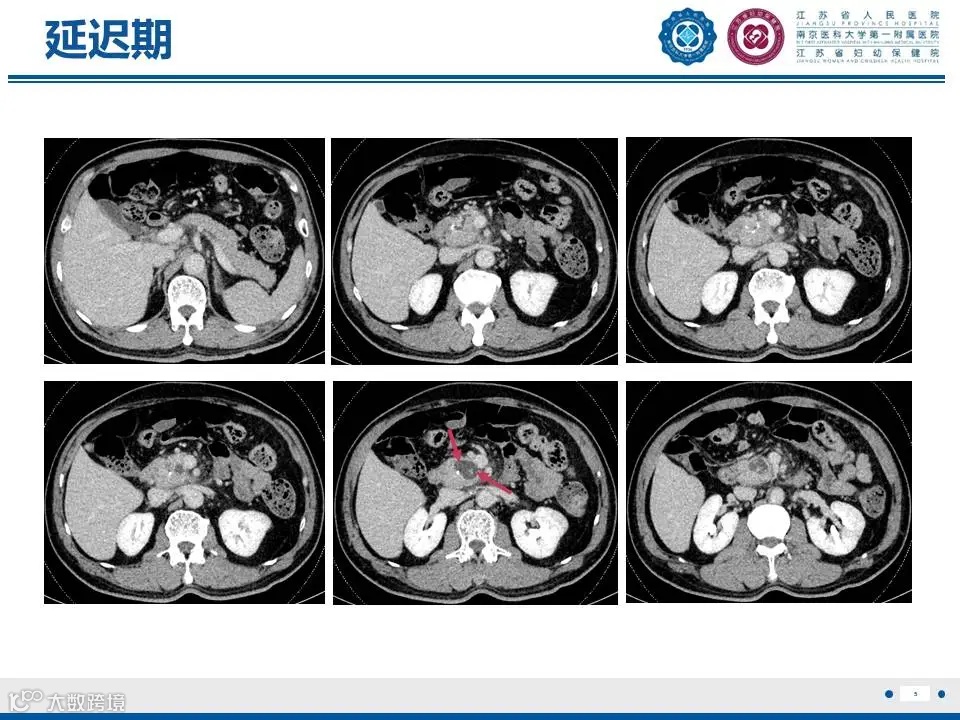

来源:江苏省人民医院放射科